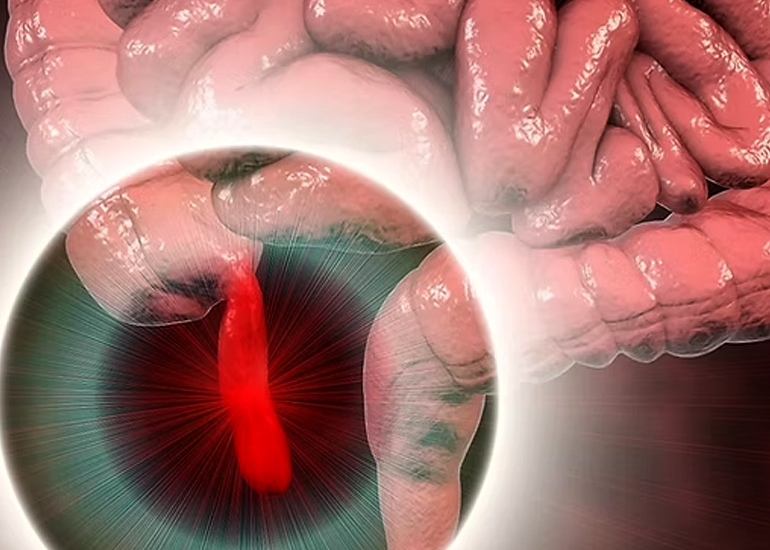

TREATMENT AVAILABLE FOR FOLLOWING DISEASES

Treatment Available